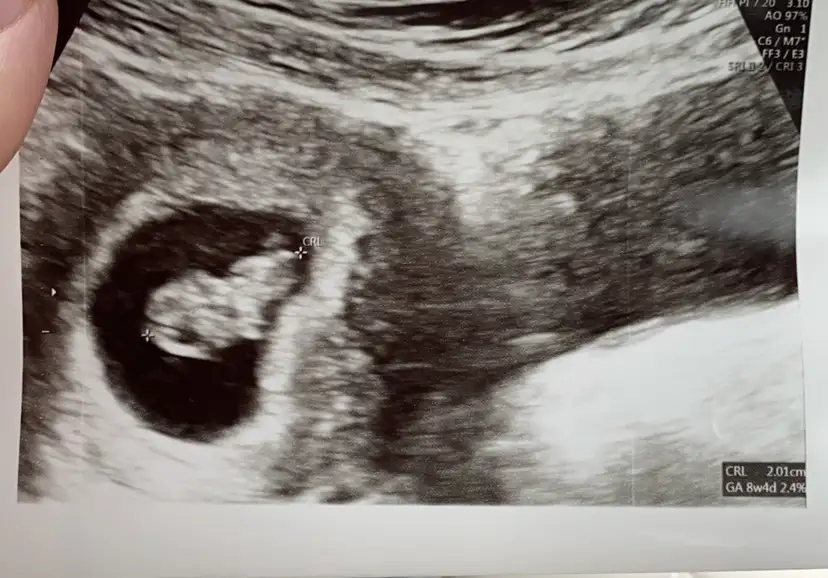

Yani bu sekildeyse erkek mi oluyor bu karın ultutasonu fotosu düz mü sayılıyo tersmi ben anlamadım bunu 9 haftalıkken almıştık bu görüntüyü😍

Benim ilk öğrenmeye gittiğim vakit yani yaklasik 6 haftalık iken sağ yerleşimliydi.Sizin ki de sağa yakın gibi ama 9 haftada ramzi teorisi turuyor mu bilmiyorum :) :)

Valla bende aslnda cin takvimi kız diyo içimdende Allahın zoruna gitmesin hep kız geçiyo rüyamdada pembe balonlar görmüstüm artık hayırlısı sağlıkla gelsinde 😍ben düz sandım bu görüntüyü sola yakın sanıyorum😂😂😂

Benim bebek 6.hafta ilk ultrasonda soldaydı 8. Haftada sağa dönmüştü. Değişiyor bence ilk tutunduğu yer önemli diye biliyorum ramzide.

6. Haftadan sonra bebiş ortalara doğru kayıyo, ben de ramziyi 6. Haftaya kadar doğru diye biliyorum:)